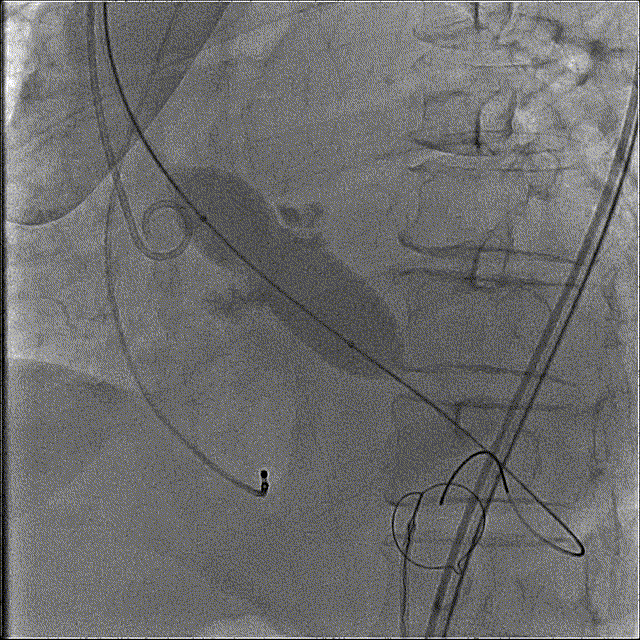

瓣膜开花造影

瓣膜工作位造影

最终释放,瓣架稳定脱钩

释放后造影,可见微量反流

未见明显反流